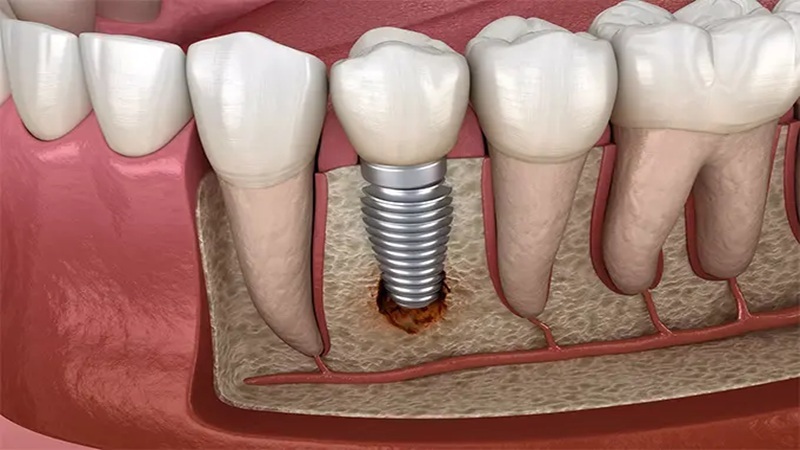

ایمپلنت دندانی شامل قرار دادن یک ریشه مصنوعی (معمولاً از جنس تیتانیوم) در استخوان فک است که به عنوان پایهای برای دندان مصنوعی عمل میکند. مراحل اصلی این فرآیند عبارتند از:

• تحلیل استخوان: در برخی موارد، استخوان اطراف ایمپلنت ممکن است تحلیل برود که این امر میتواند به عدم پایداری ایمپلنت منجر شود.